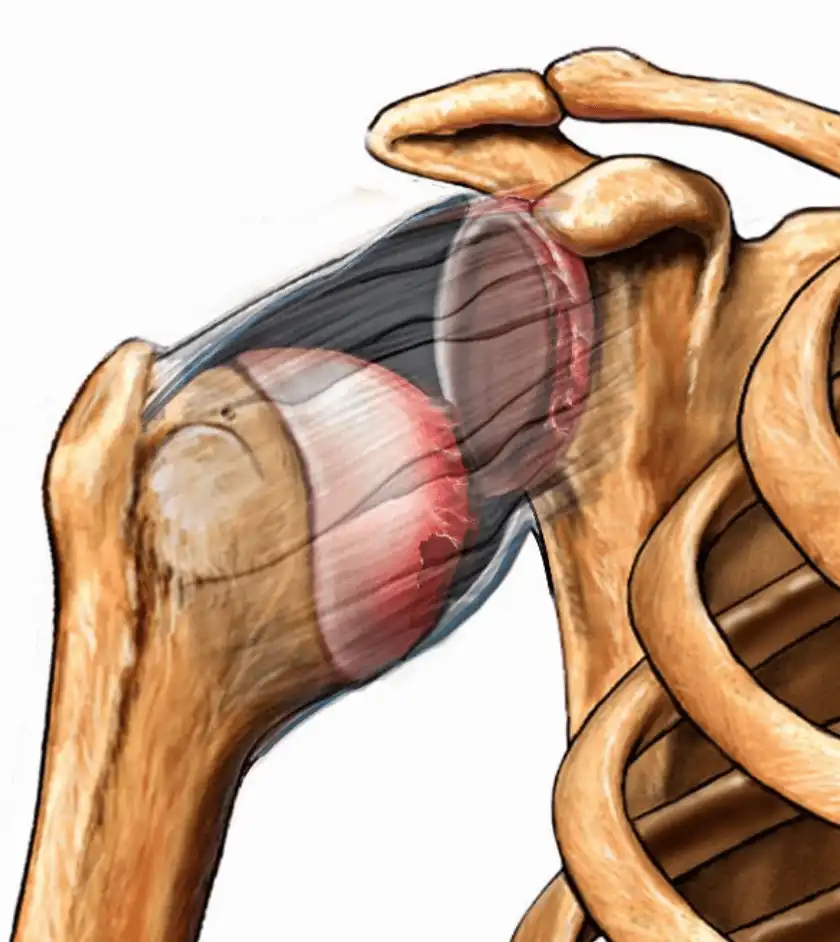

پارگی تاندون روتاتور کاف (Rotator cuff) | علائم، دلایل، روشهای درمان و فیزیوتراپی تخصصی در سال1405 ادامه مطلب »

همهچیز درباره عمل پارگی تاندون شانه در سال 1405 | مراحل جراحی، نکات طلایی و مراقبتهای بعد از عمل ادامه مطلب »

جراحی مفصل شانه در سال 1405 | قیمت، نکات طلایی و راهنمای قدمبهقدم برای بازگشت بدون درد ادامه مطلب »